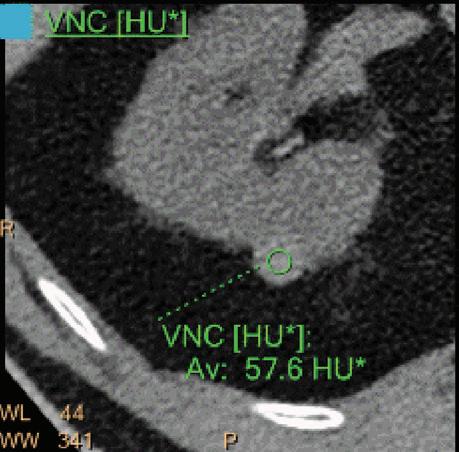

Virtual No Contrast (VNC) [HU]

This result imitates a monoenergetic 70 keV CT scan without contrast injection, and is derived from a CT scan with contrast enhancement. The quantified iodine content is translated to an HU number and subtracted from the contrast enhanced 70 keV images.

Note: Because the iodine quantification is based on the two-component model (water-iodine), any deviation from water dispersion is interpreted as nonzero iodine component. In particular, bone (calcium) is interpreted as a mixture of water-like and iodine-like material. The VNC algorithm does not attempt to separate bone and iodine. Therefore, the CT number [HU] of bone in VNC images is roughly half of its value in the original 70 keV image. A study comparing VNC and true non-contrast (TNC) images showed that the attenuation values from VNC in most abdominal tissues are within 10 HU of those obtained from unenhanced images, with the notable exception of subcutaneous fat.11,12 These results demonstrate the potential of VNC images to serve as a surrogate for unenhanced images in some clinical settings (Figure 4).

A hyperdense lesion (65 HU) is visible on the right kidney on the conventional CT images obtained after contrast enhancement. The TNC image is shown in the upper right corner. The lower row displays spectral results in the Magic Glass, from left to right: conventional CT image, VNC image, Iodine no Water image, and iodine density image. Comparison between measurements performed on the TNC (55.4 HU) and VNC images (57.6 HU) demonstrates only a minor difference between them (difference = 2.2 HU), showing that the VNC images could perfectly replace the TNC images in this clinical scenario. Iodine concentration measurements in the same region of interest show values of no more than 0.3 mg/ml which can be considered as negligible. In other words, there is no contrast medium uptake in the lesion which can thus be considered as benign. The hyperdensity is of a hemorrhagic cyst.